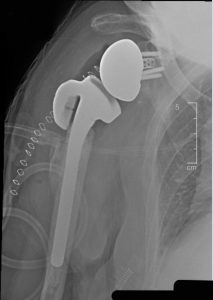

The Humeral Augmented Tray is the first implant of its kind. It replaces the greater tuberosity, a part of the shoulder that may be absent or deficient, fractured and/or reabsorbed due to disease. The HAT was designed to be used in combination with the Equinoxe Platform Shoulder System for reverse procedures and was designed to help improve joint mechanics and stability for patients with proximal humeral bone loss. This unique implant can also be used with an extension for more severe proximal bone loss cases.

The first surgeries with the Humeral Augmented Tray were performed last week in Florida by Bradley Schoch, MD, of the Mayo Clinic in Jacksonville, and design team surgeon Howard Routman, DO, of JFK Medical Center in Lantana.

“The patients who need this implant have either previously undergone surgeries which failed, suffered fractures of the humeral head, or have congenital abnormalities that leave them with deficient tuberosities, which prevent them from doing what they want,” said Dr. Routman. “This implant allows them to return to what they love, and I feel very honored to have been part of the design team and one of the first to use this prosthesis.”